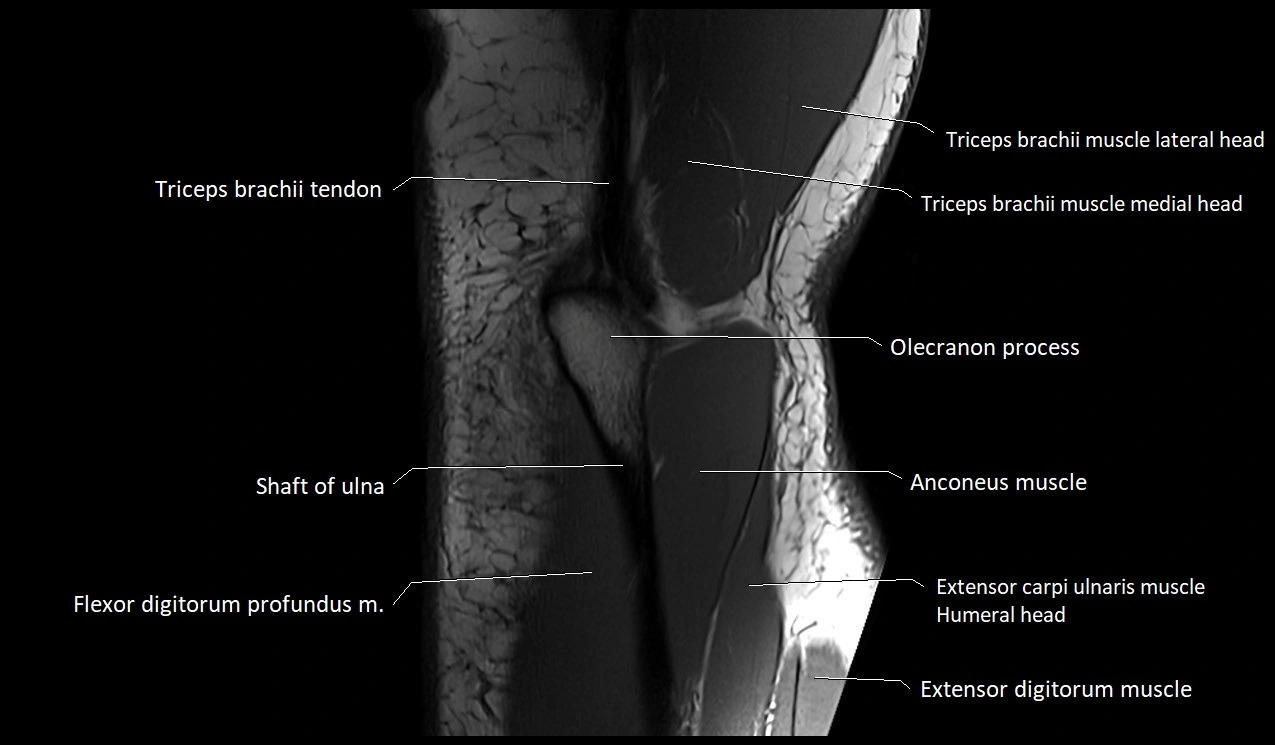

MRI image

image